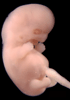

Carnegie Stage 19 (47 post-ovulatory days)

Most embryos at stage 19 are approximately 47-48 post-ovulatory days old and measure 17-20 mm in length. Distinguishing criteria for this stage include straightening of the trunk, the limbs extend nearly directly forward, toe rays are prominent, but interdigital notches have not yet appeared in the foot.

Although some of the photographs below show abnormal embryos, the animations and MRI slice images all depict normal embryos. Abnormal embryos are noted in the titles of the large photos when they are opened.